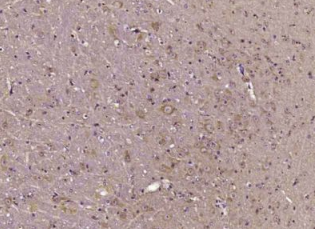

多聚甲醛固定,石蜡包埋(小鼠脑);用柠檬酸钠缓冲液(pH6.0)煮沸15min后获得抗原;用3%过氧化氢阻断内源性过氧化物酶20分钟;阻断缓冲液(正常山羊血清)在37℃下30min;用(磷酸-Akt1(Tr34))多克隆抗体进行抗体孵育。1:400在4°C下过夜,然后根据SP试剂盒(兔子)说明和DAB染色进行操作。